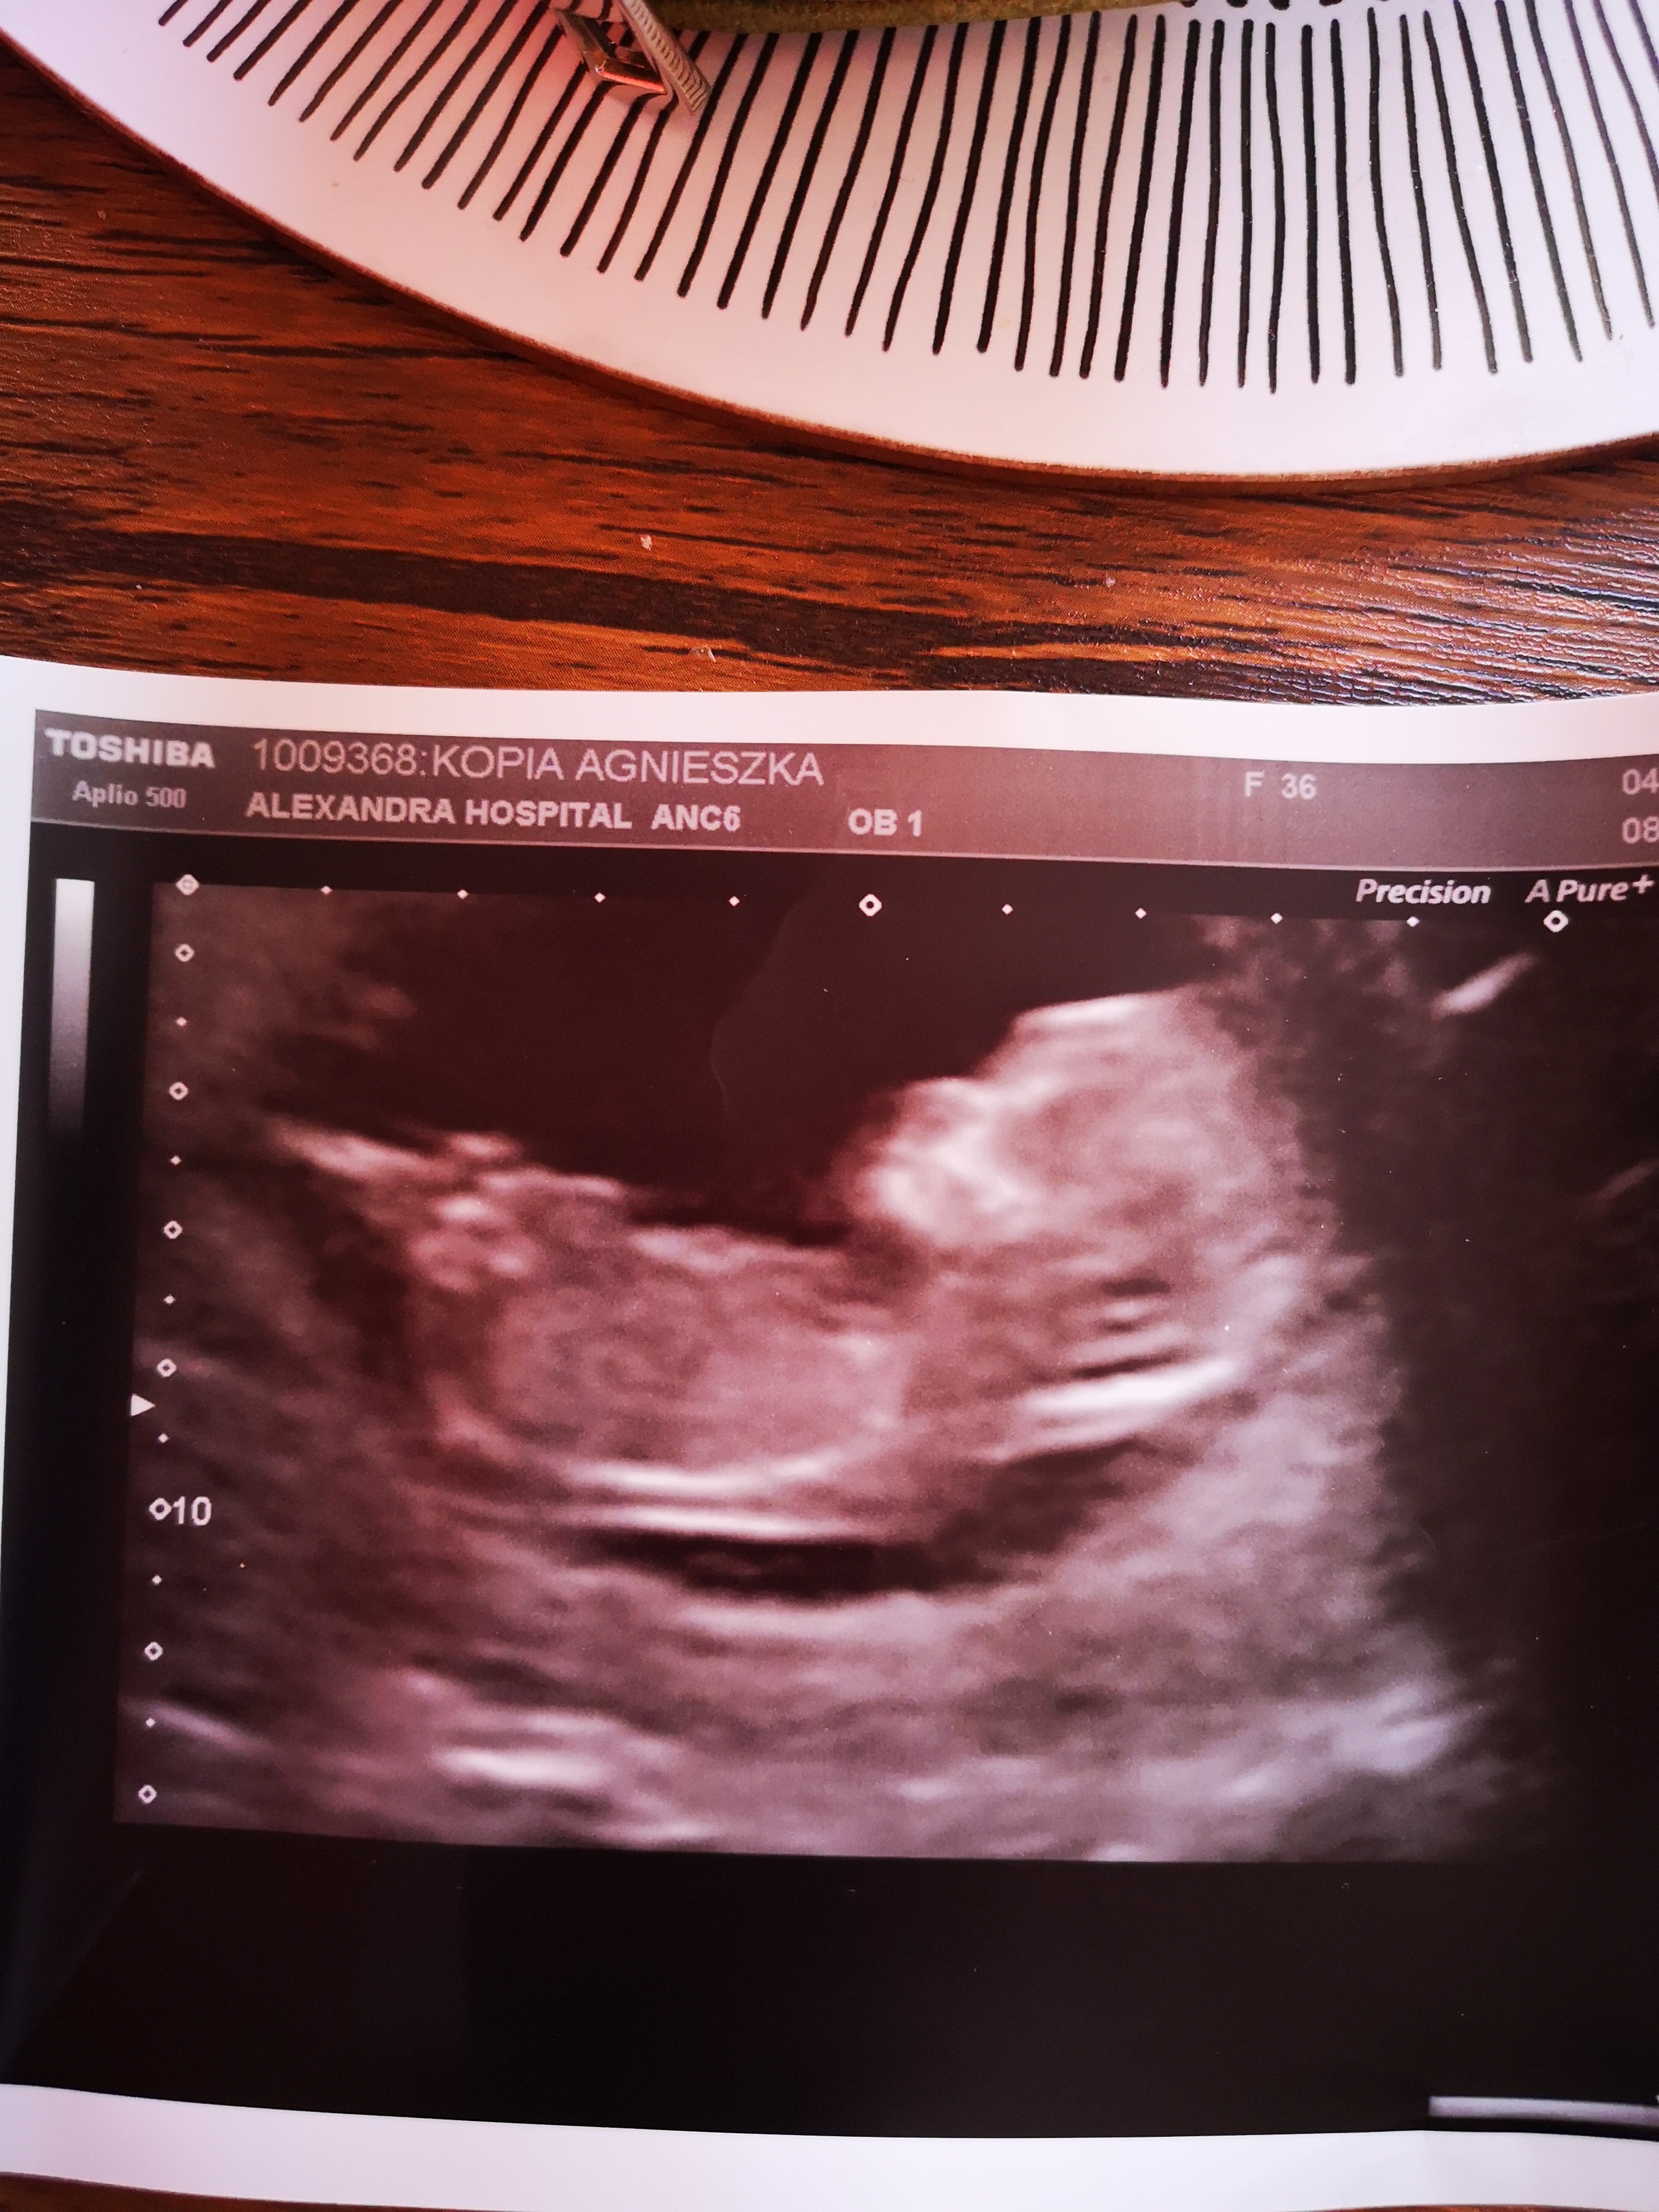

Nie wiem czy chłopak czy dziewczynka ale na ostatnim zdjęciu ślicznie trzyma rączkę za głową. [emoji3][emoji3]

Czesc dziewczyny jak myślicie to chłopiec czy dziewczynka [emoji6]